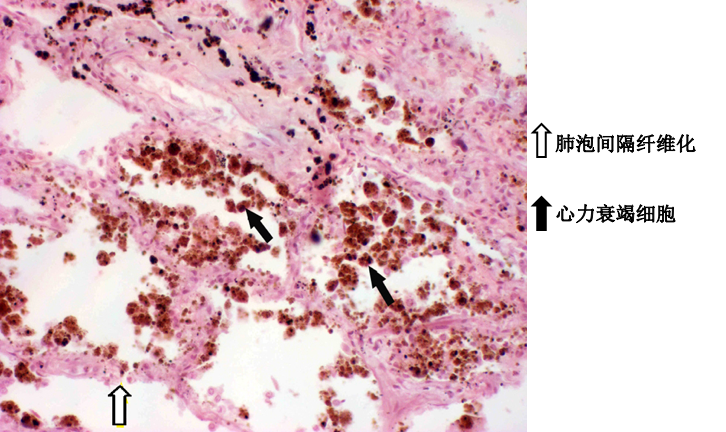

(3)病理变化: 急性肺淤血:肺体积增大、暗红色,切面流出泡沫状血性液体。 镜下:肺泡壁增厚、毛细血管高度扩张充血,部分的肺泡腔内可见水肿液及多少不等的红细胞、巨噬细胞。有些巨噬细胞吞噬了红细胞并将其分解,胞浆内形成含铁血黄素,称为“心力衰竭细胞”。 慢性肺淤血:随着肺淤血时间的延长,大部分肺泡腔内出现多量漏出液,造成肺水肿。长期慢性的肺淤血,可使肺泡壁增厚和纤维化,肺质地变硬,肉眼呈棕褐色,称为肺褐色硬化。